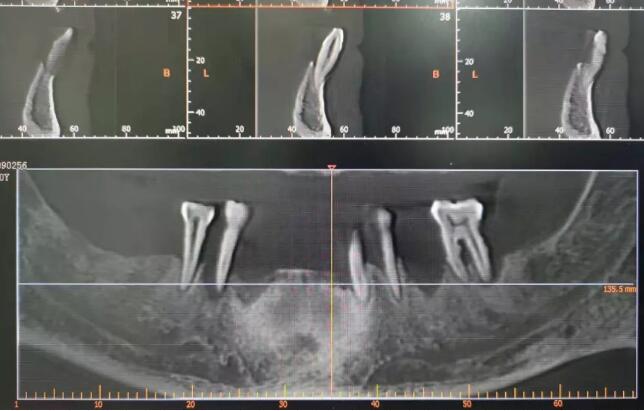

孙主任看了爸爸的CT片,骨量还不错,能符合做多颗种植的条件。他又问了一下爸爸的身体健康的综合情况,我如实告知血压一直临界,而且有点心血管疾病的先兆指标,孙主任跟我说,还是需要带爸爸做做体检,多了解一些情况,医学是个综合的学科,我们大家都谨慎一些更好。

(笔者父亲检查时下颌剩余牙情况的CT截图)